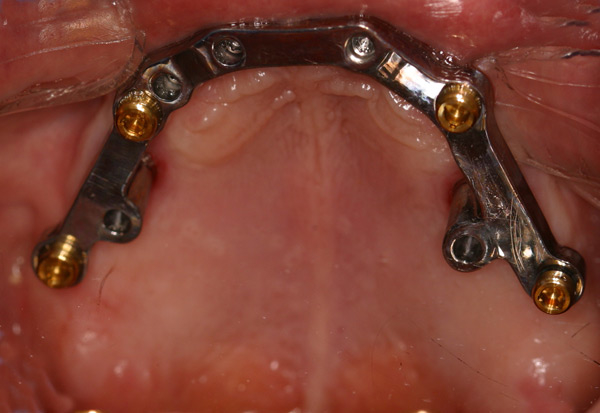

Problem: This patient had a series of problems that resulted with tooth loss. He also has a problem with sleep apnea. He wanted something fixed and stable.

Plan: Our plan… placed four implants on the lower with a fixed/hybrid prosthesis. Placed five on the upper arch with a titanium bar and snap attachments to allow a special one of the kind sleep apnea device.

He really likes his new smile and he gets a great nights rest as well.